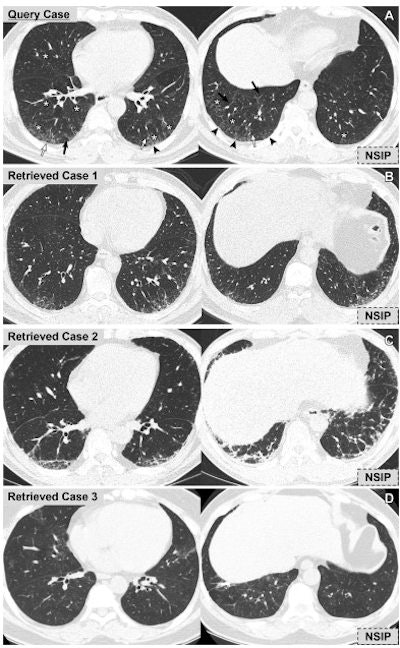

The authors chose 80 CT exams out of the 288 to be test exams for the content-based image retrieval search engine; the engine chose the top three similar CT images for these 80 exams from the database by comparing disease patterns that had been quantified by a deep-learning algorithm.